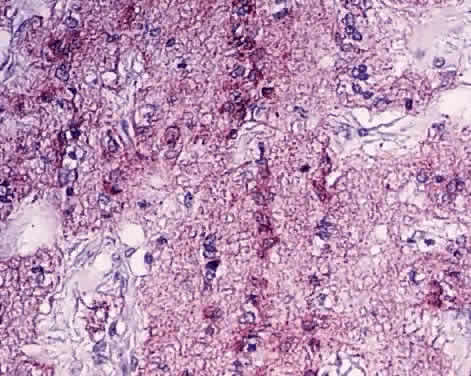

MICROGLIA. Microglia are the phagocytes of the CNS. In the normal optic nerve, these cells are ordinarily present in small numbers, and most are found within bundles of axons, with some situated adjacent to the glial septa and to blood vessels.17 Normally, these cells are irregularly oval, containing small nuclei and many long and slender branching processes. Under electron microscopy, microglial cells have small, heterochromatic nuclei. The cytoplasm shows vacuoles, granular endoplasmic reticulum arranged in long, narrow strands, and various inclusions, including large dense bodies, lamellar bodies, myelin bodies, and other forms of cellular debris (see Fig. 3).17 Immunohistochemical studies reveal that microglia in the retina are positive for Griffonia simplicifolia B4-isolectin, CR3 complement receptor, leukocyte common antigen (CD45), and antimacrophage marker CD68 (Fig. 5).22,23 These cells do not contain glial filaments.

Fig. 5. Immunohistochemistry in the longitudinal section of the optic nerve. CD68-positive cells (red) are scattered in the optic nerve and represent microglia. × 660.

Microglia usually reside quietly in the optic nerve, but they can be easily activated by trauma, inflammation, edema, or degenerative conditions. The activated microglia become oval or rod-shaped, their small nuclei enlarge and become elongated, and the complicated cytoplasmic processes are withdrawn. Activated cells can phagocytize a variety of materials and can express major histocompatibility complex class I and II molecules (see Fig. 5).22,23